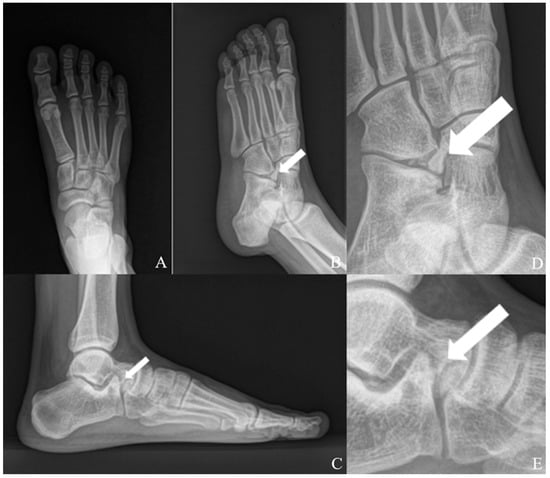

Multiple Calcaneus Secundarius Ossicles Presenting with Anterior Foot Pain: A Case Report Highlighting Characteristic Imaging Features

Background: Calcaneus secundarius (CS) is an accessory ossicle located at the anterior aspect of the calcaneus and is typically an incidental and asymptomatic radiographic finding. However, it may become symptomatic following trauma or repetitive mechanical stress and can mimic anterior calcaneal process fracture or tarsal coalition, leading to diagnostic confusion. The presence of multiple independent CS ossicles represents a rare morphological variant and a potential source of diagnostic ambiguity. Methods: We report the case of a 19-year-old male soldier who presented with progressive anterior foot pain following soccer activity without a clearly identifiable traumatic event. Radiographs, computed tomography (CT), and magnetic resonance imaging (MRI) were performed to evaluate the underlying pathology. Results: CT demonstrated two separate, well-corticated accessory ossicles adjacent to the anterior calcaneal process without bony continuity. MRI revealed focal bone marrow edema (BME) at the calcaneus–ossicle interface, suggesting mechanical irritation at the fibrous connection. Due to persistent symptoms and concordant imaging findings, surgical excision was performed, resulting in immediate pain relief and return to full daily and sports activities without recurrence at the 1-year follow-up. Conclusions: Multiple CS ossicles may produce fragment-like imaging appearances and increase the risk of misdiagnosis. Recognition of characteristic imaging features, particularly well-corticated ossicles and focal BME at the ossicle–calcaneus interface, together with clinical correlation, is essential for accurate diagnosis and appropriate management in patients with persistent anterior foot pain. Full article